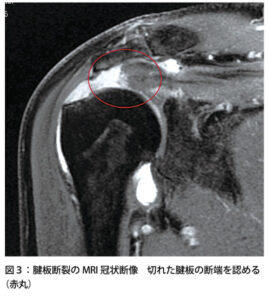

肩関節の腱板損傷・断裂

| 病態 | 腱板に亀裂が入る疾患。多くの場合は棘上筋腱から断裂が始まり、腹側や背側に伸長する。外傷による損傷よりも加齢に伴う退行性変化が圧倒的に多く、80歳代では50%に認める。腱板断裂すると腱が自然修復することはなく、手術による修復を行うほかない。 |

| 症状 | ※高齢者の約7割が無症状 ①肩の疼痛:挙上時痛や患側臥位による夜間痛(インピンジメントにより生じる) ②可動域制限:疼痛肢位回避によるものが多い(他動的には制限を認めない) ③筋力低下:進行すると関節不安定性により生じる |

| 所見 | 視診:進行すると棘上筋や棘下筋が萎縮(五十肩では見られない) 触診:棘上筋断裂部の触知、他動的な可動域制限を認めない |

| 検査 | 【画像検査】 エコー:断裂部を確認 MRI:T2強調像で断裂部が高信号となる ![]() |